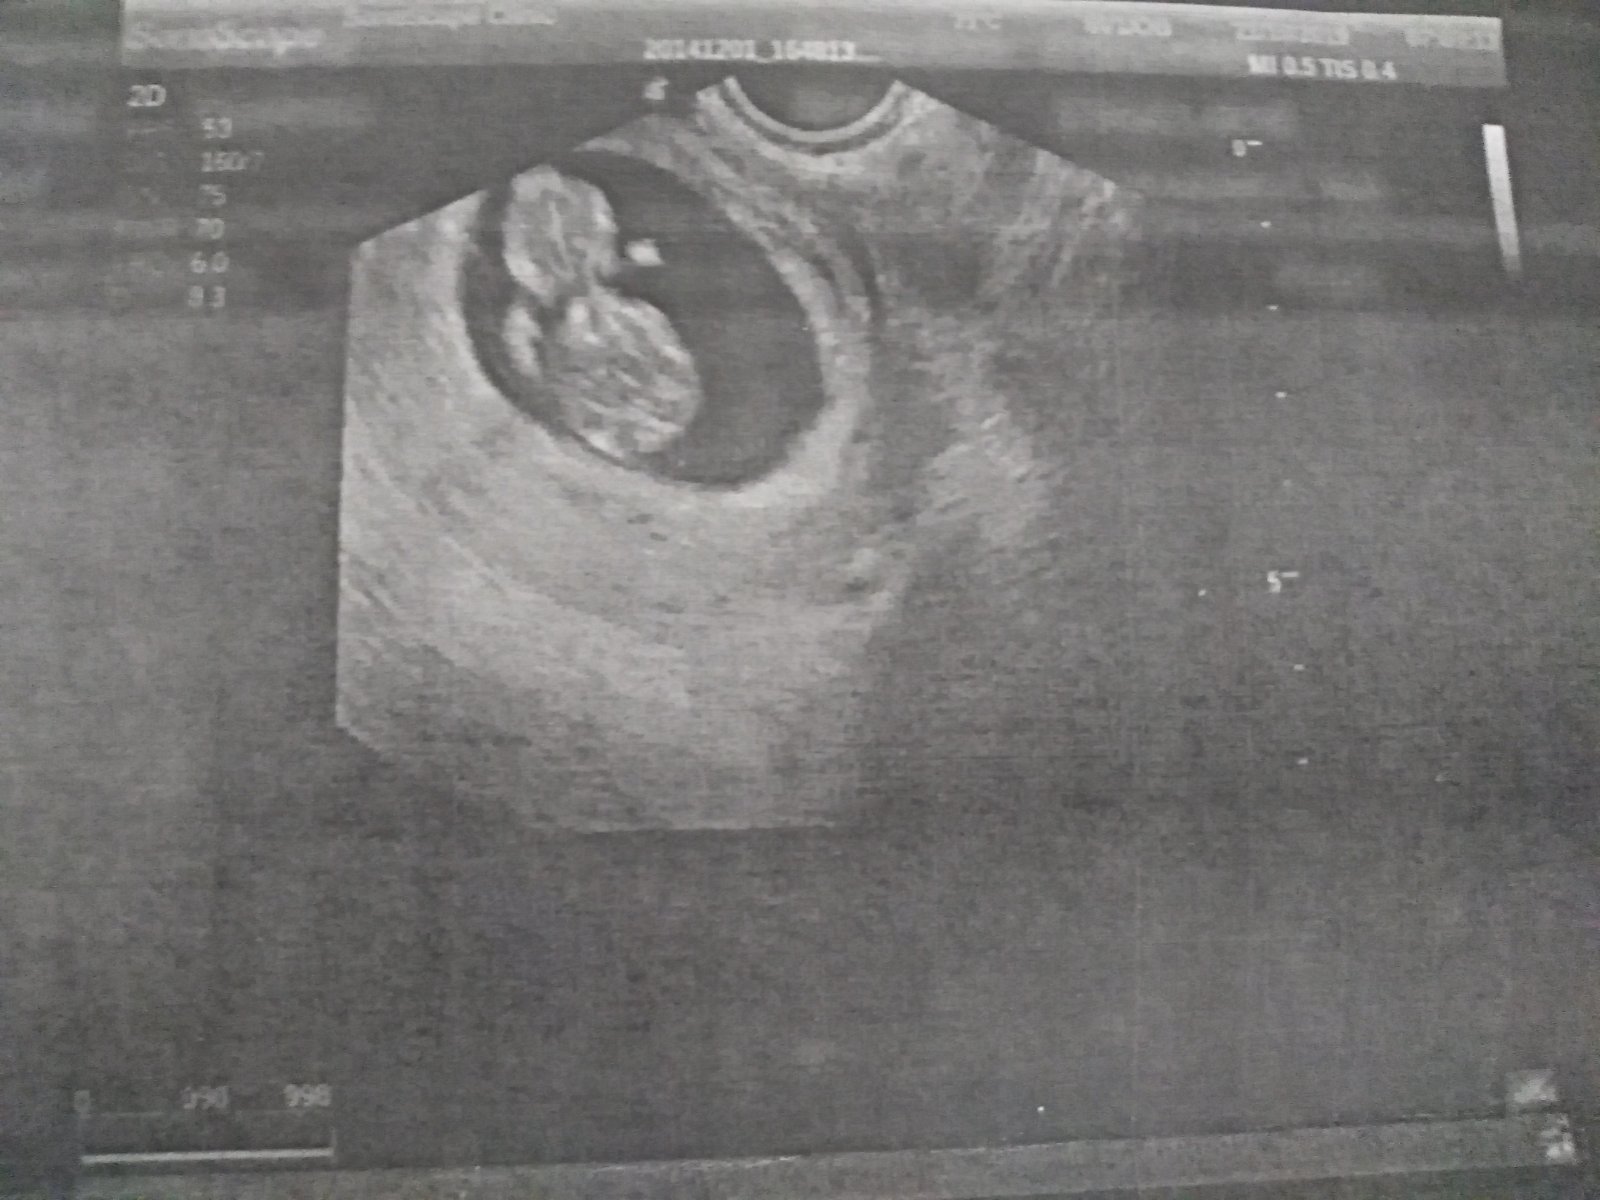

@racochejlek87 V 6tt uz bilo a ted sem byla 7+6 a taky busilo krasneeee

Ahoj holky, tak dalsi kontrola zamnou a vse v poradku 😍